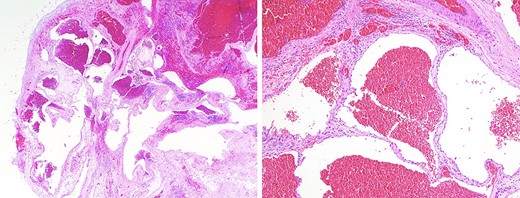

(a) low-power microscopic view (hematoxylin and eosin stain; 20X magnification) showing a well-circumscribed tumor composed of ectatic blood-filled spaces separated by intervening fibrous stroma with scattered lymphoid aggregates, entrapped fat and smooth muscle proliferation; (b) medium-power microscopic view (hematoxylin and eosin stain; 100X magnification) highlighting the presence of endothelial cells lining blood-filled spaces, confirming the diagnosis of a benign hemangioma.

Despite imaging, it may be difficult to differentiate mediastinal hemangiomas from other lesions of the mediastinum without the aid of histopathological confirmation. Histologic features divide hemangiomas into three types: capillary hemangiomas, CHMs, which encompass 90% of cases, and a mixed type [12]. Fig. 2a and2b demonstrates low and medium power views of the lesion, highlighting the presence of endothelial cells lining blood-filled spaces, intervening fibrous stroma, and scattered lymphoid aggregates, diagnostic for CHM. Immunohistochemistry staining was positive for ERD, CD-31, CD-34, confirming a hemangioma and negative for D2-40, effectively ruling out lymphangioma (Fig. 3a and3b).